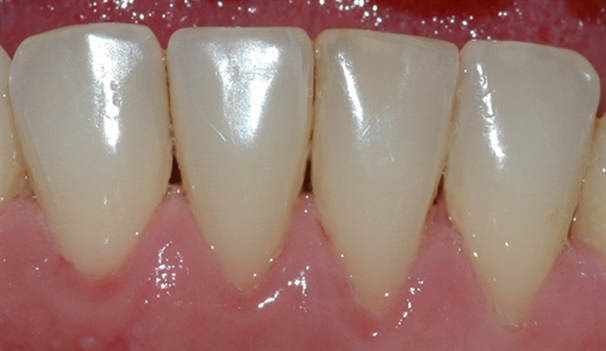

perio stor 5

Bildet viser et tannsett med synlig tannsten og misfarging.